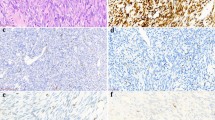

The immunohistochemical analysis showed immunoreactivity localized to the nucleus of the synovial lining cells (Fig. 2). A few stromal cells adjacent to the synovial lining cells also showed nuclear reactivity. The inflammatory cells were negative for HMGIC. Immunoreactivity was identified in 11/21 of the OA-affected cases and in 1/4 of the normal cases (Table 1). There was no obvious correlation between the immunohistochemistry results and the degree of synovitis. However, positive staining was greater in areas featuring multilayering of synovial lining cells and increased cellularity (Fig. 2). The positive nuclei were observed among scattered negative cells, arguing against the possibility of false-positive staining in these experiments.

A, Hematoxylin and eosin section of the synovial biopsy from Case 37 (40 ×). The synovium shows reactive changes with increased cellularity and multilayering of synovial lining cells. The area within the black rectangle is shown after immunostaining with HMGIC-specific antibodies at higher magnification in Panel B (400 ×). The immunoreactivity was localized to the cell nucleus of the synovial lining cells. Negative control was performed by omitting the primary antibody (C).